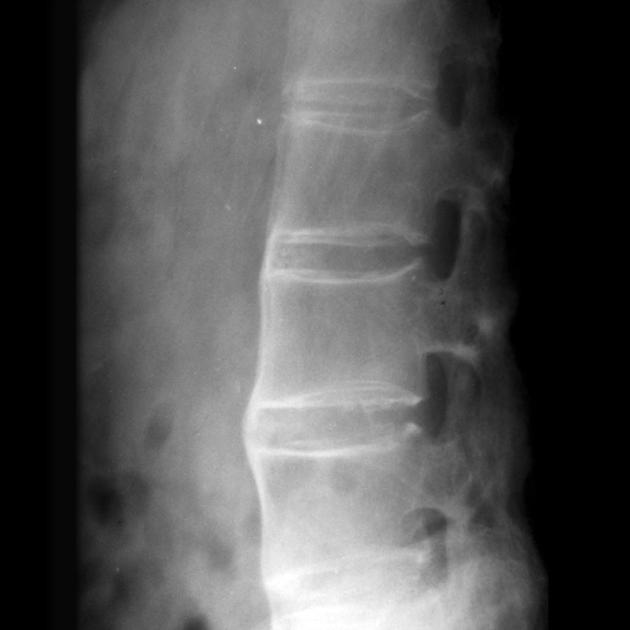

强直性脊柱炎的临床表现与症状

说起强直性脊柱炎,你可能会觉得这是个生僻的词汇。 但实际上,这个看似陌生的疾病正在悄悄影响着我们身边的人。 据统计,全世界约有5400万人,中国约有500万...